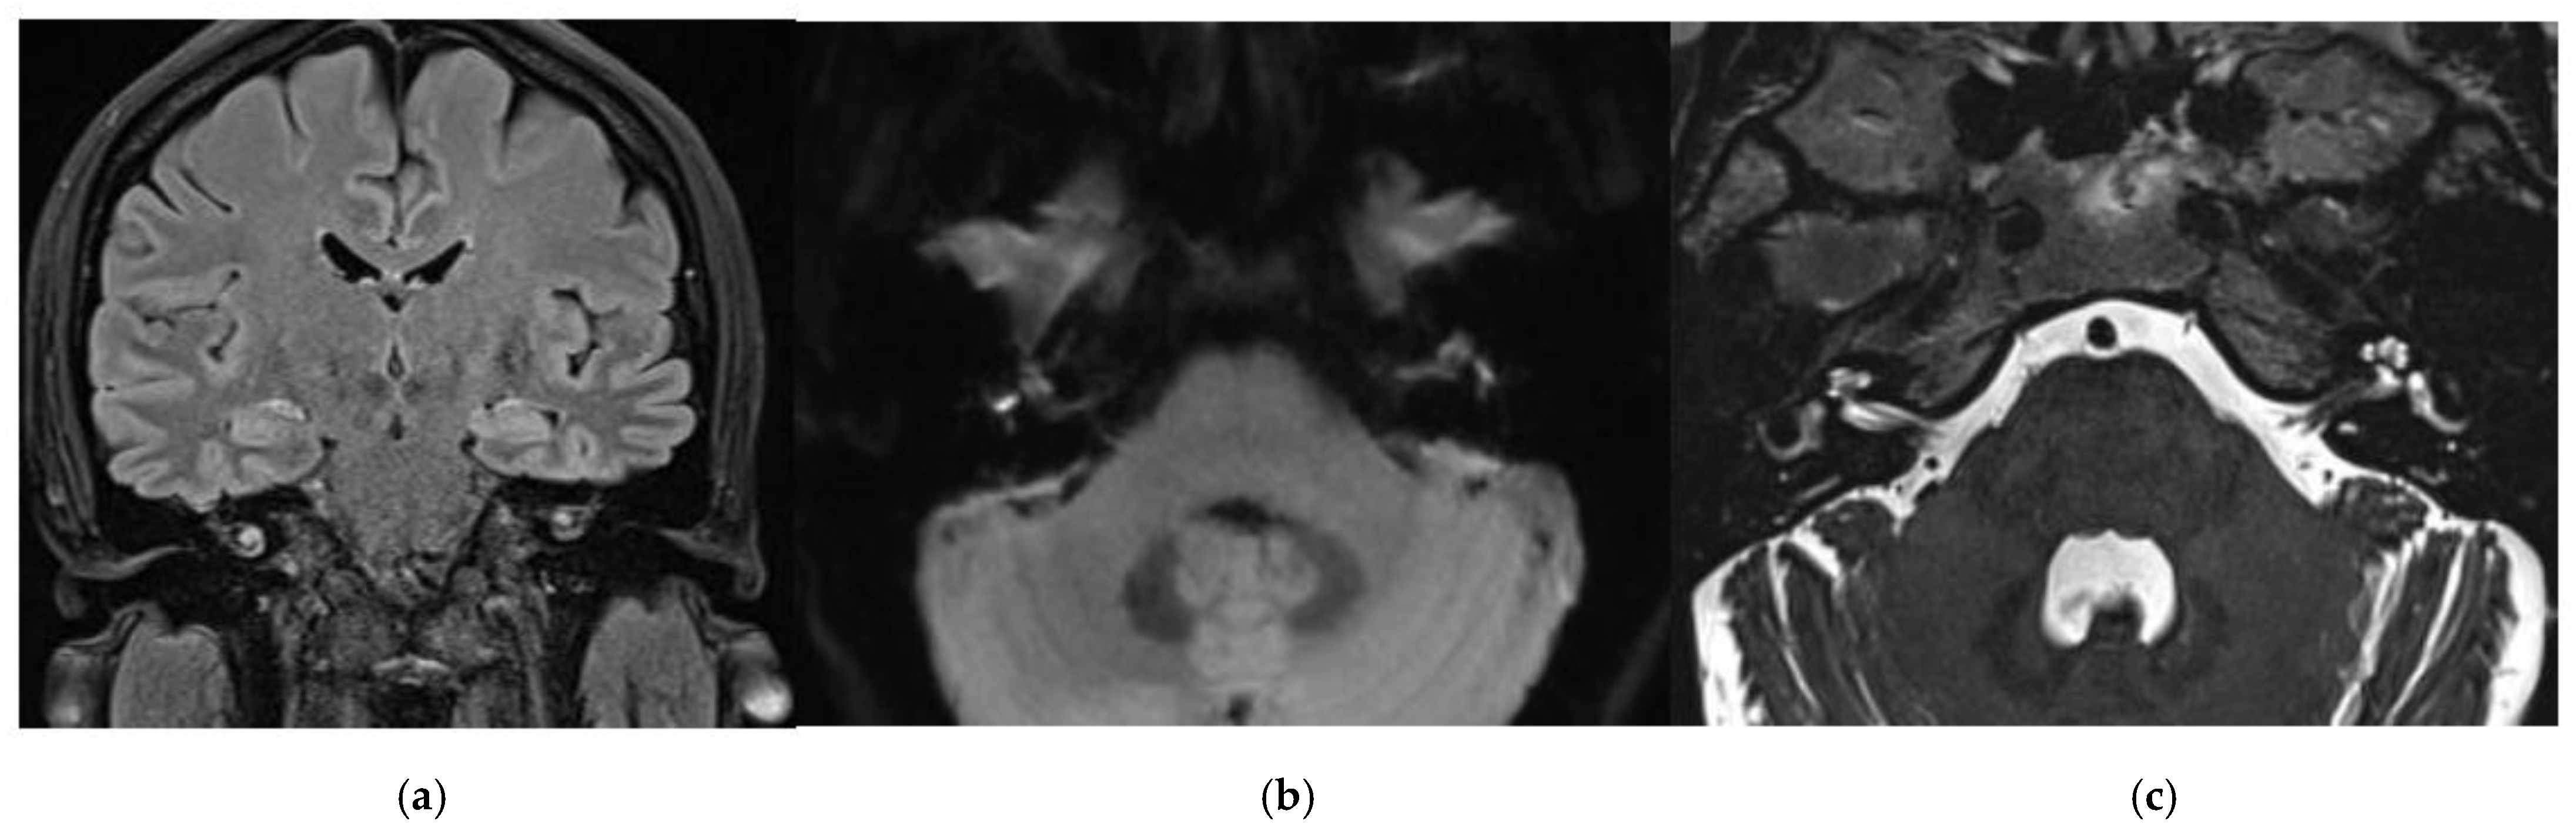

3.1. CASE 1

3.2. CASE 2